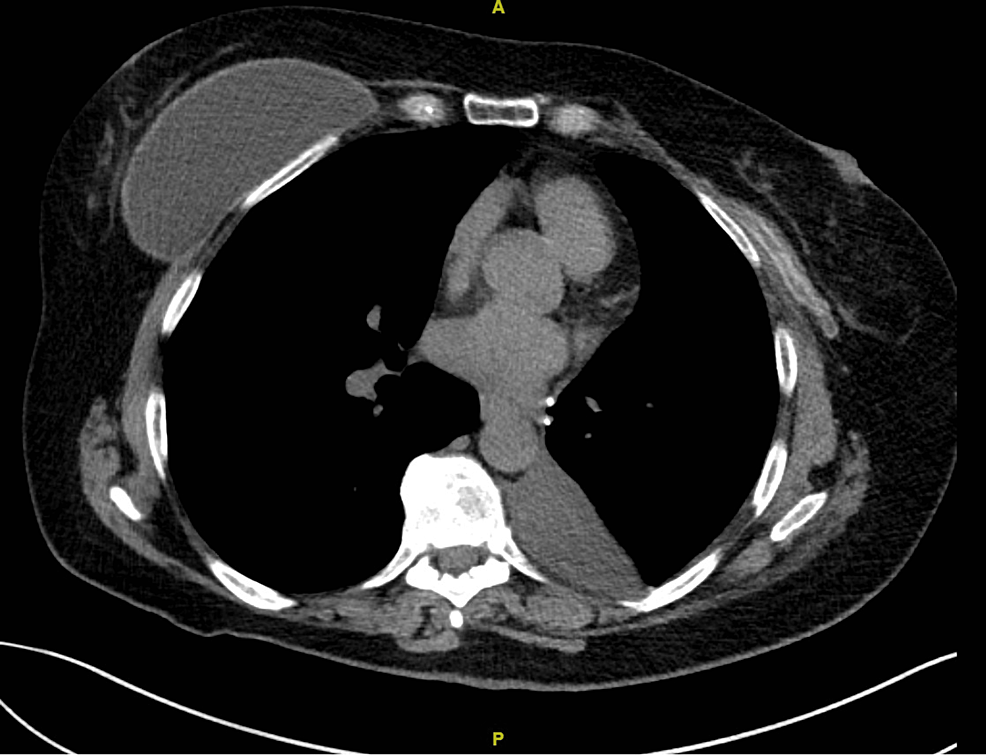

Pneumothorax Causes, symptoms, and treatment Chest Deflated Meaning It’s often described as a feeling of pressure or heaviness on the chest, discomfort in the chest or throat, a feeling of being short of. Hyperinflated lungs occur when the air sacs in the lungs, called alveoli, become overinflated with air. A penetrating chest wound allows outside air to enter the chest, causing the lung to collapse. A pneumothorax is. Chest Deflated Meaning.